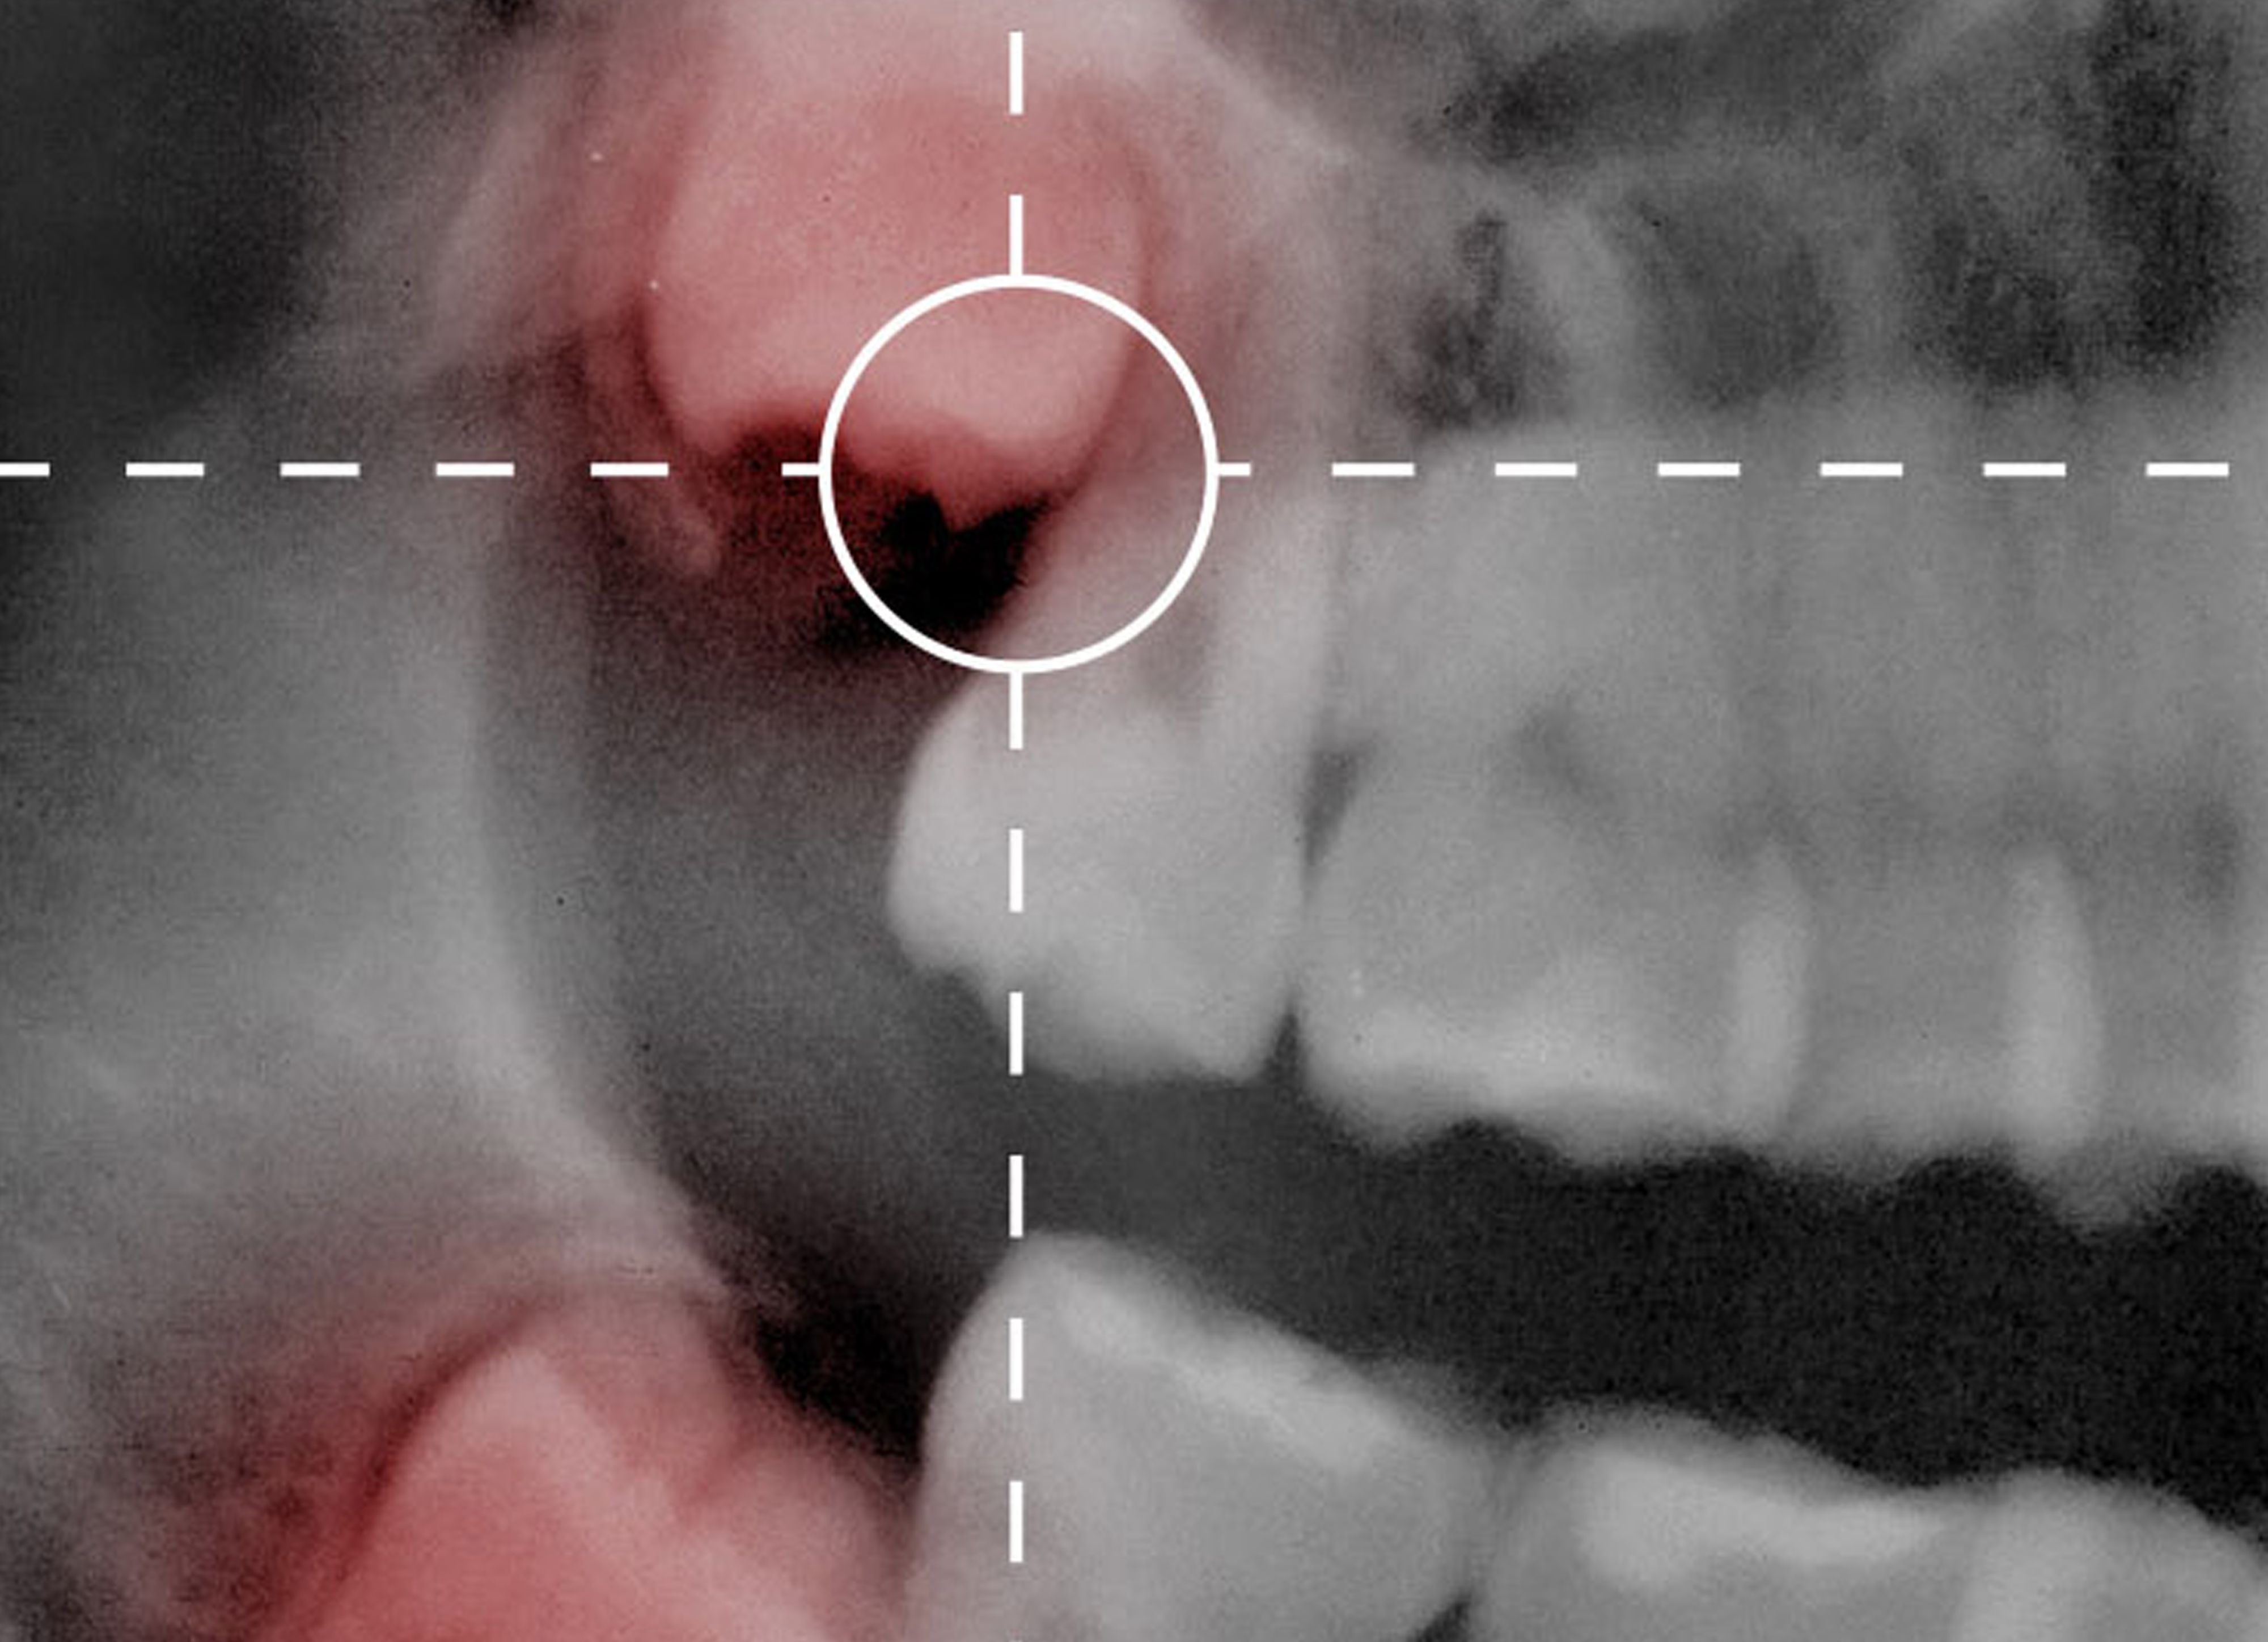

La periodoncia es una disciplina de la Odontología que se encarga del tratamiento de las enfermedades periodontales. Las más frecuentes son las gingivitis, que es la inflamación y sangrado de encías; y la periodontitis, pérdida de hueso, ligamento periodontal y cemento.

Su no tratamiento puede conllevar a la pérdida de la pieza dental.

En Clínica Dental Aizcorbe realizamos tanto tratamientos quirúrgicos como conservadores de enfermedades periodontales.